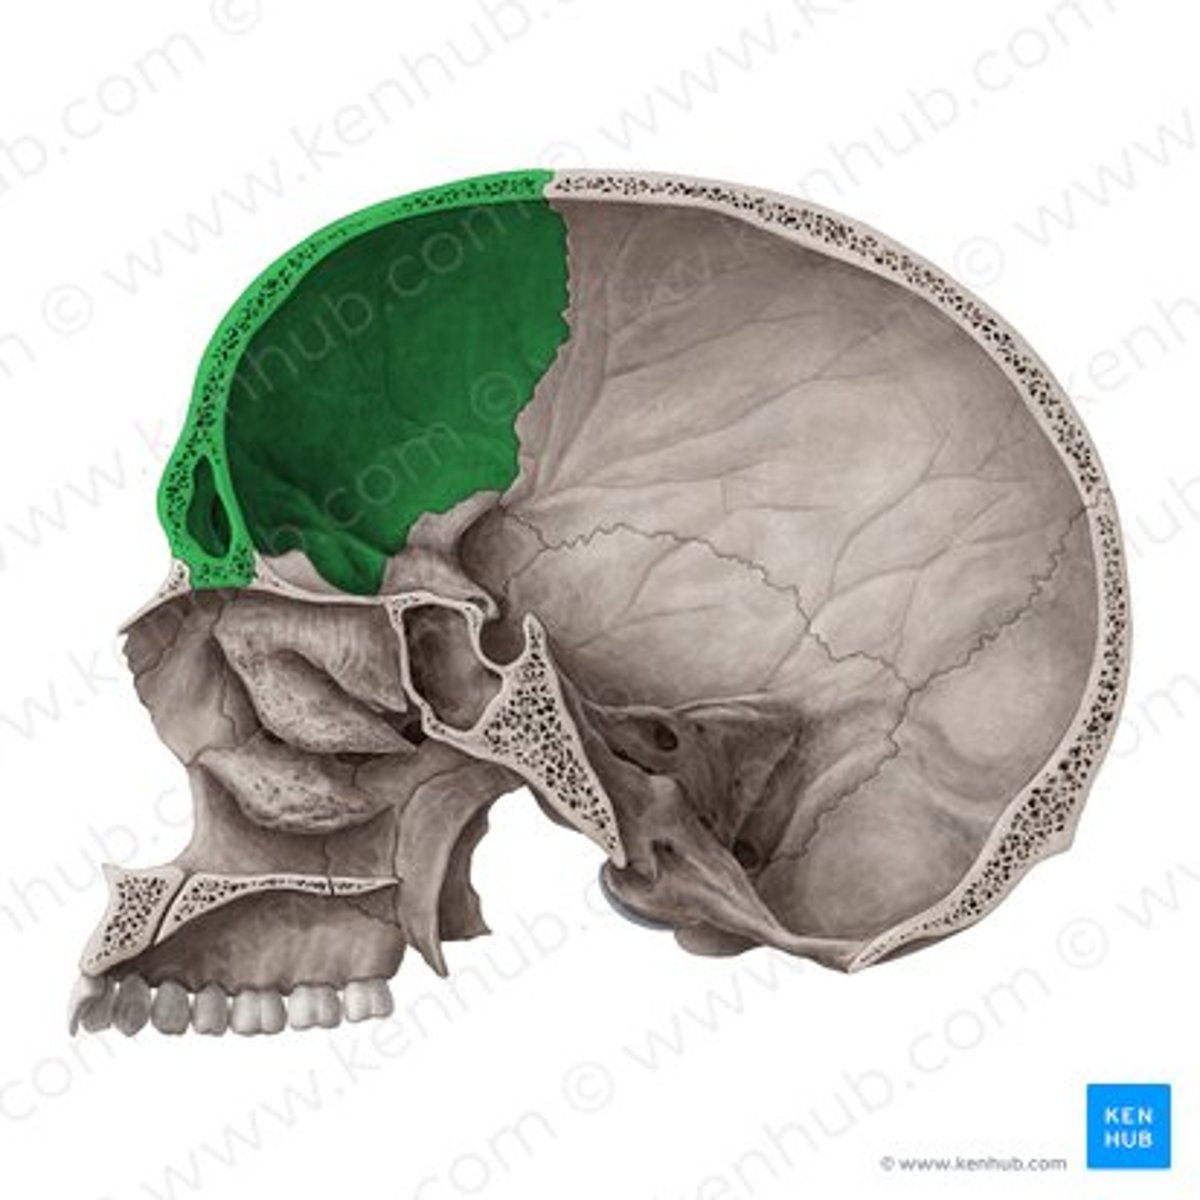

frontal bone